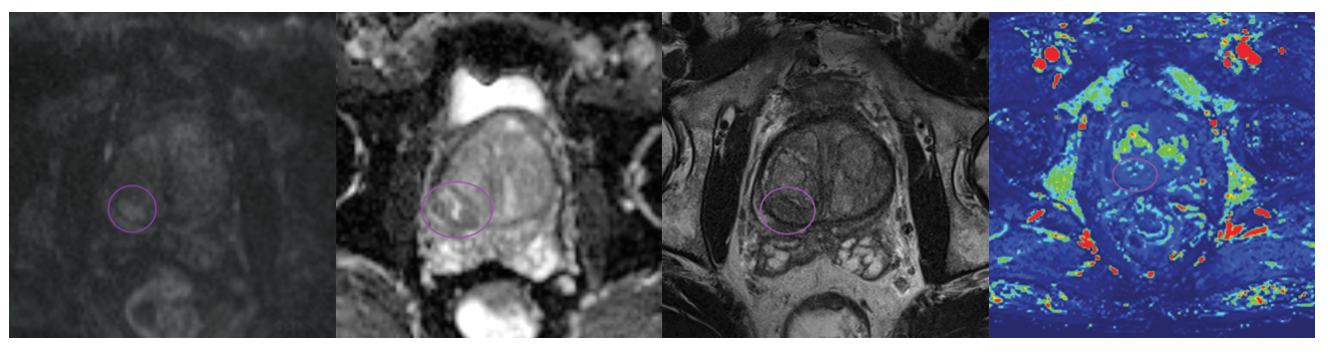

Đánh giá ung thư TLT trên MRI bằng PI-RADS. Phiên bản mới 2.1 (2023)